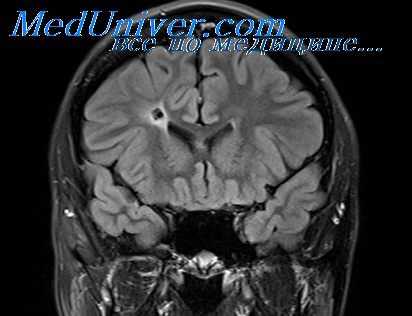

Диагностика абсцесса головного мозга по КТ, МРТ

МРТ головного мозга — более точный метод диагностирования. При проведении МРТ на первых стадиях формирования абсцесса мозга (1-9 сутки) энцефалитический очаг выглядит: на Т1-взвешенных изображениях — гипоинтенсивным, на Т2-взвешенных изображениях — гиперинтенсивным. МРТ на поздней (капсулированной) стадии абсцесса головного мозга: на Т1-взвешенных изображениях абсцесс выглядит, как зона пониженного сигнала в центре и на периферии (в зоне отека), а по контуру капсулы сигнал гиперинтенсивный. На Т2-взвешенных изображениях центр абсцесса изо- или гипоинтенсивный, в периферической зоне (зоне отека) гиперинтенсивный. Контур капсулы четко очерчен.